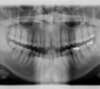

Les radios avant le traitement